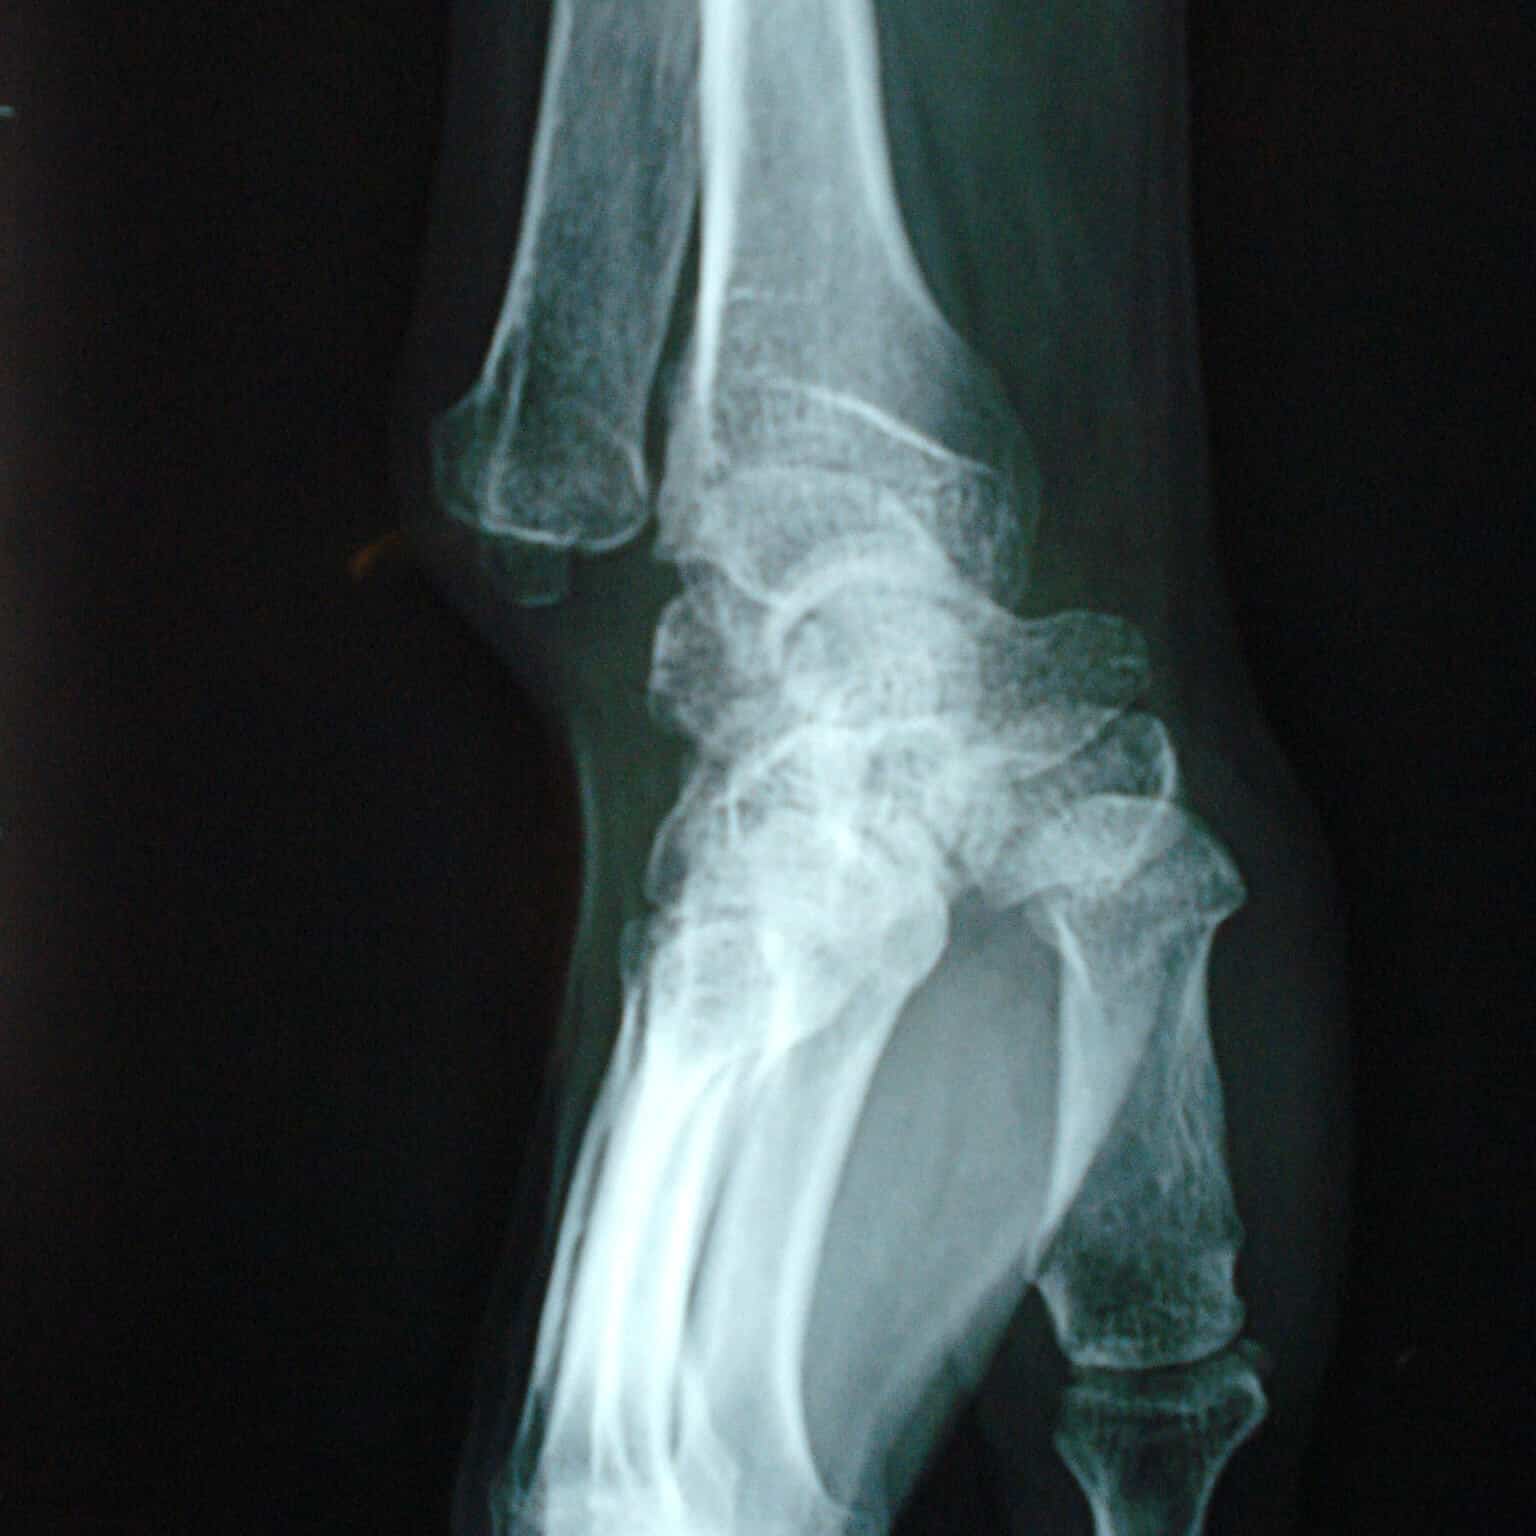

entorse luxation rétro lunaire du carpe

Expulsion du semi lunaire sur une luxation rétro lunaire du carpe